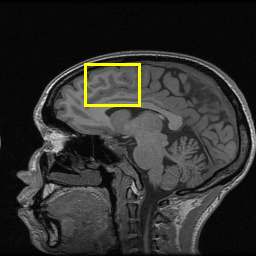

Moreover, in Fig. 6, we provide a visual comparison of the reconstruction results of these models. We can see that EAMRI has fewer bright spots in the heatmaps, which means less error between the EAMRI reconstructed image and the ground truth image. Meanwhile, according to the zoomed-in images of the selected areas, we can observe that our EAMRI can reconstruct more clean and accurate edges. This further validates the validity of EAMRI. Both the quantitative and the qualitative results for the single-coil MRI reconstruction demonstrate the effectiveness of EAMRI.

(a)

(b)

(c)

(d)

(e)

(f)

(g)